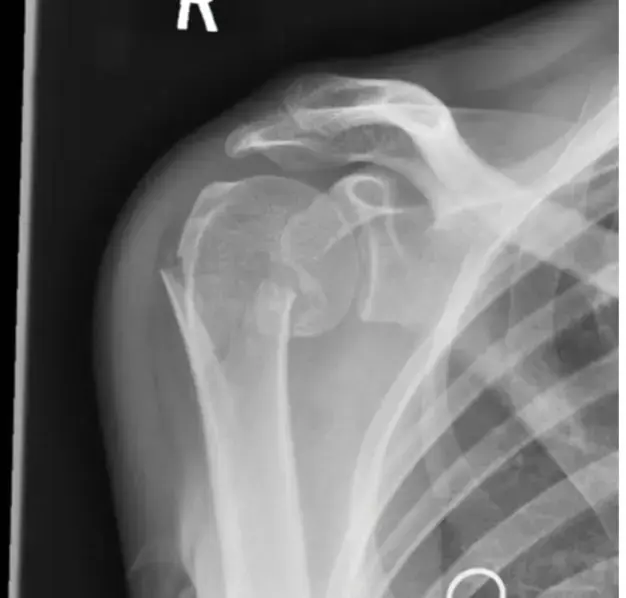

صورة توضيحية لـ دليل شامل لإصابات وكسور الأطراف السفلية المعقدة وإدارة الحوادث المتعددة (Polytrauma) | الأستاذ الدكتور محمد هطيف، صنعاء

• الأشعة السينية (X-ray): لتقييم الكسور وتحديد طبيعتها (مفتوحة، مغلقة، داخل المفصل، متفتتة).